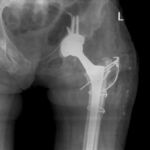

2.1. Учебная и клиническая база кафедры